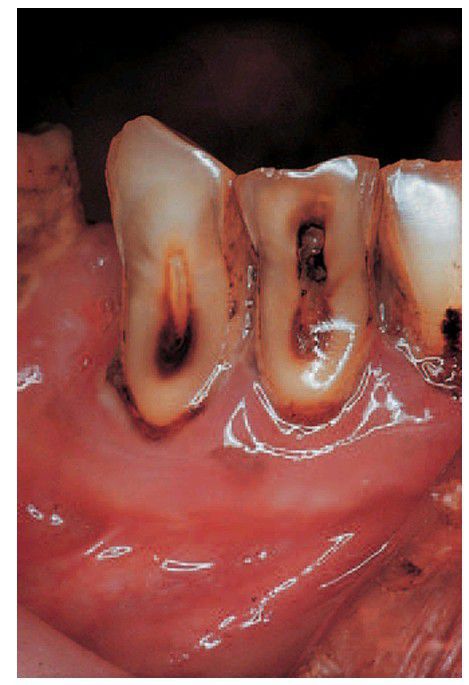

Mixed pattern tooth loss.

In this case, an element of erosion may be present. Note the shiny polished surface produced by abrasion.